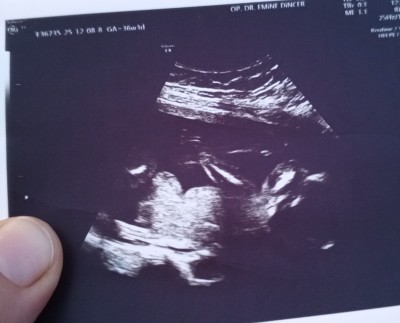

Cinsiyet tahmini yapapilirmisiniz

Gebelik haftası 15+1